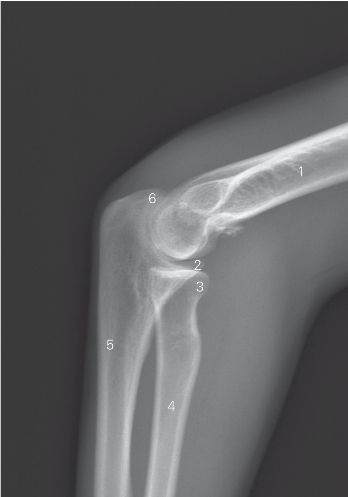

图7-3 肘关节侧位DR平片

1 肱骨 humerus 2 尺骨冠突 coronoid process of ulna

3 桡骨小头 capitulum radii 4 桡骨 radius

5 尺骨 ulna 6 尺骨鹰嘴 ulnar olecroanon